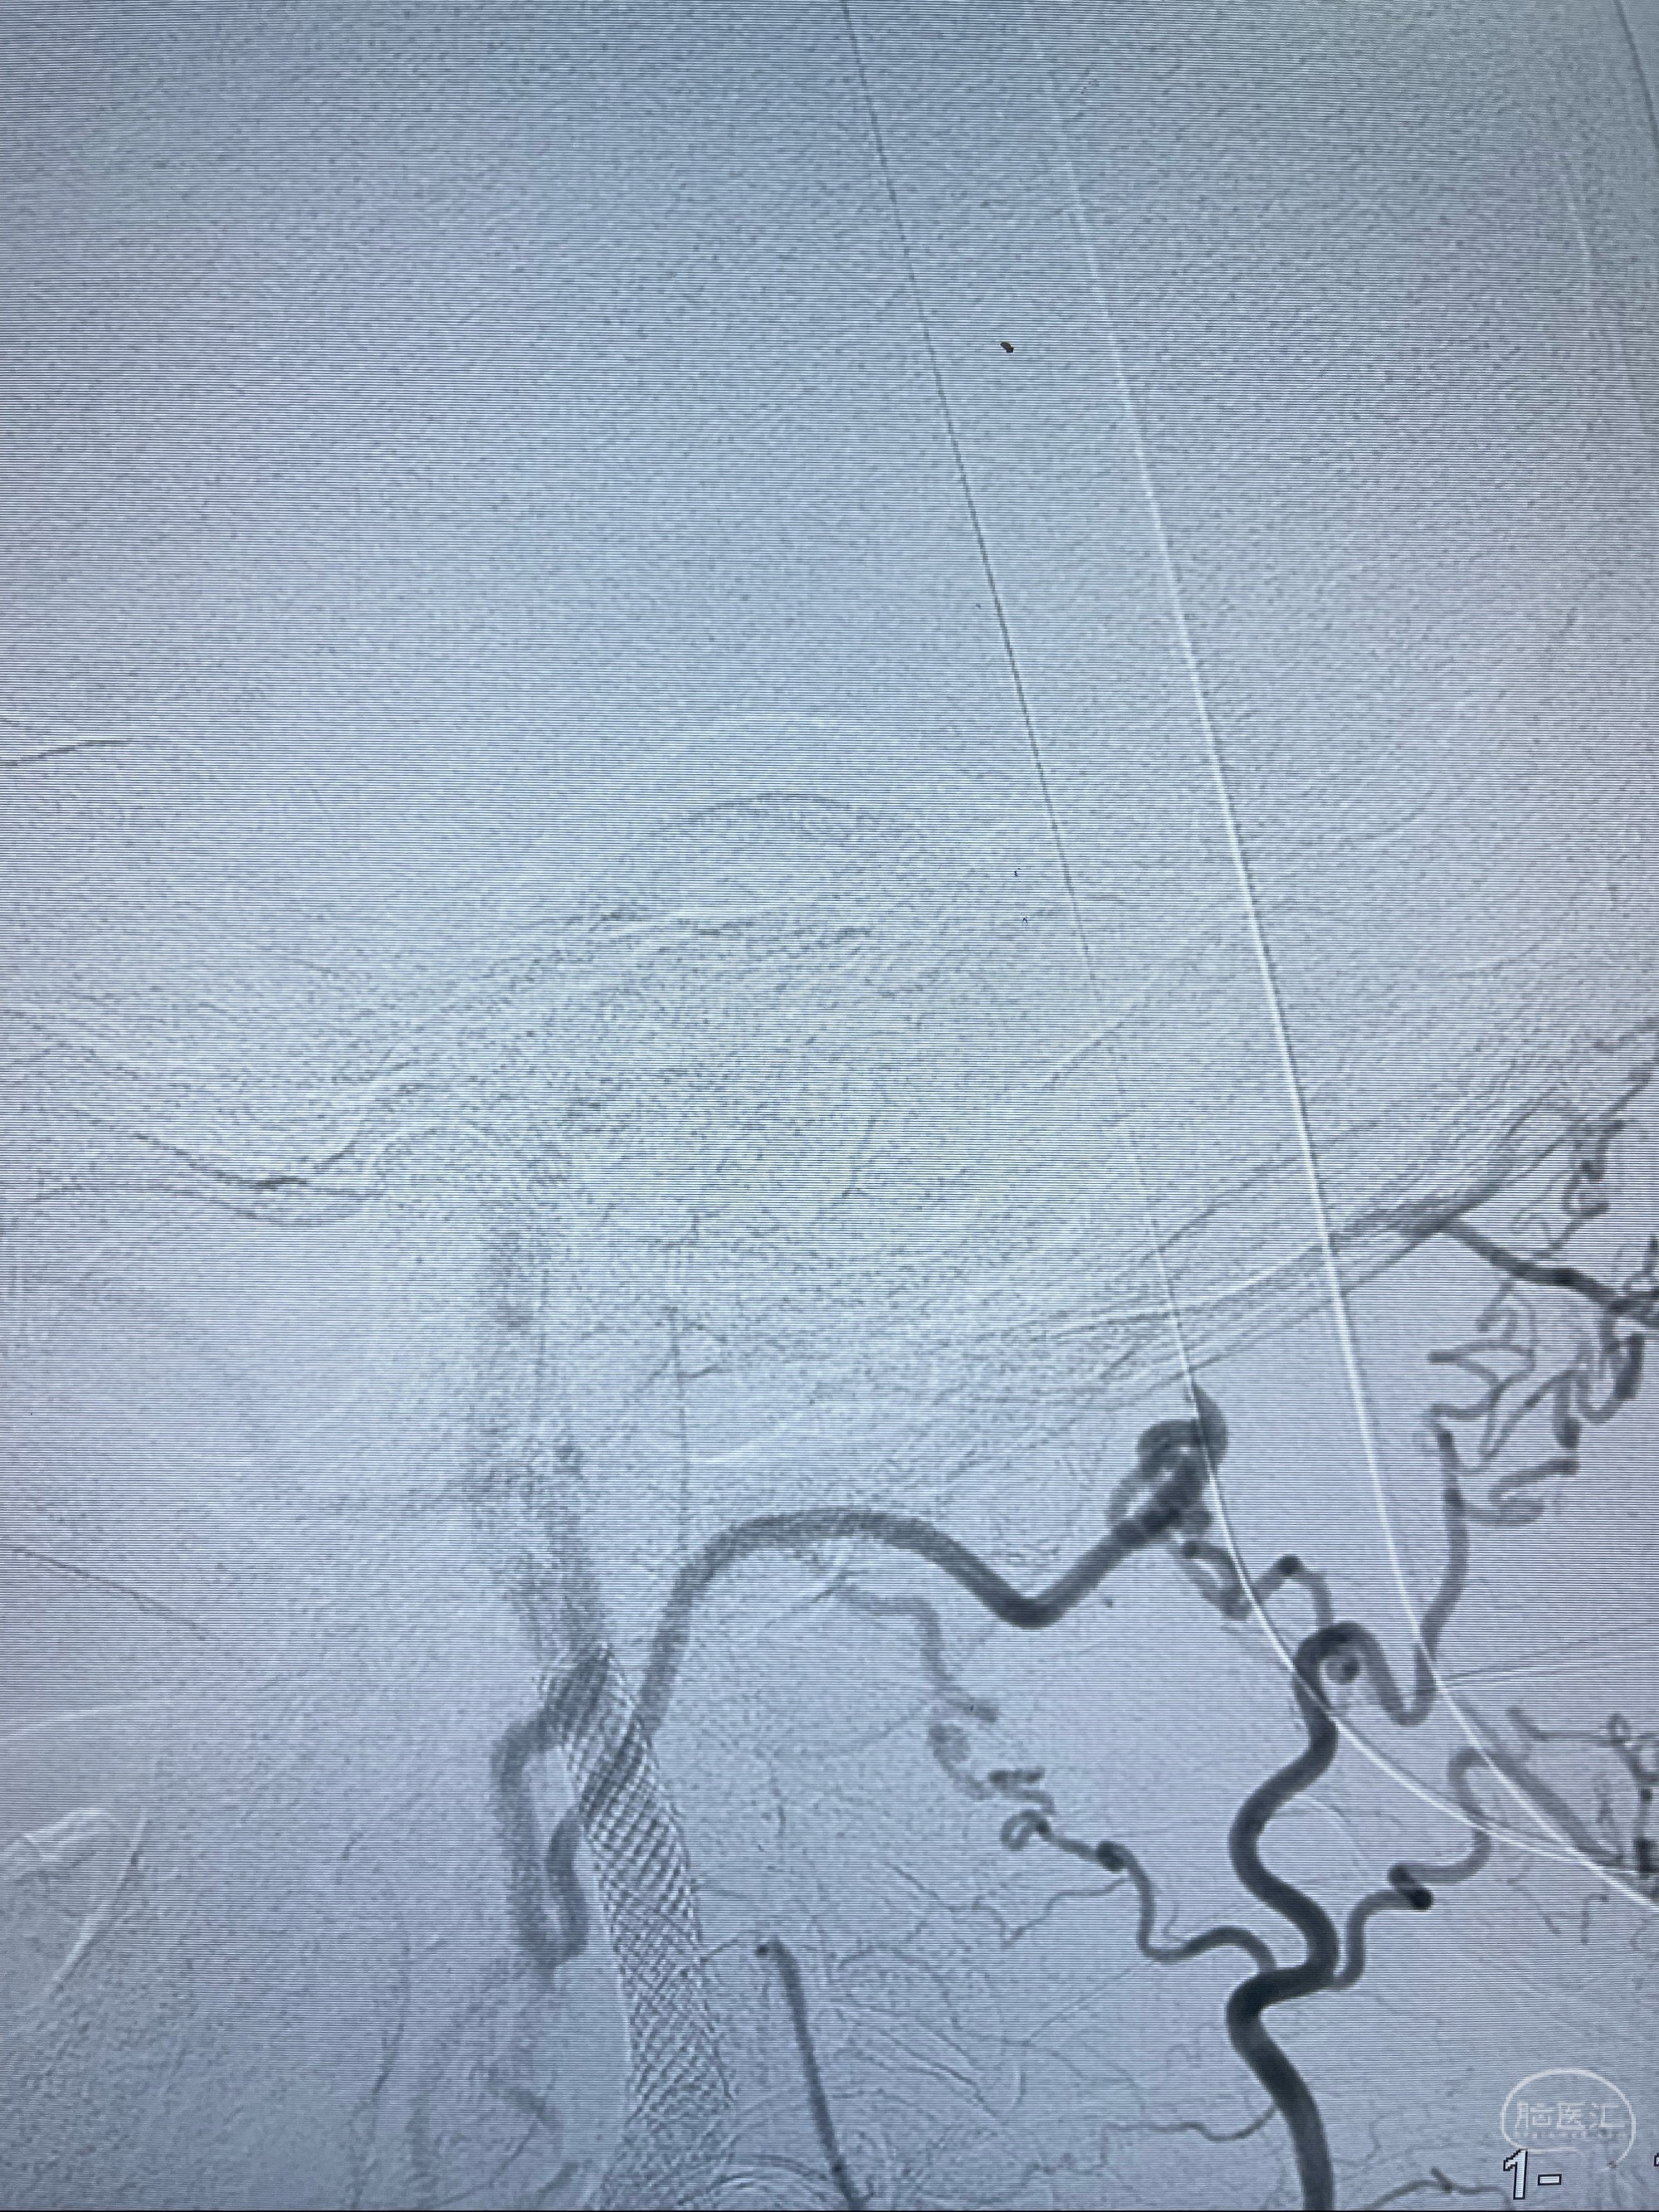

2023-07-10DSA:右侧颈内动脉岩骨段夹层伴中偏重度狭窄改变,左侧颈总动脉闭塞、右侧颈外动脉由右侧肋颈干甲颈干吻合代偿

箭头所示为颈内动脉岩骨段重度狭窄,结合MRI,考虑为肿瘤侵犯右侧颈内动脉

箭头以近至支架段管腔不规则狭窄

经导引导管造影显示支架远端颈内动脉不规则狭窄伴局部充盈缺损,同时行全身肝素化5ml